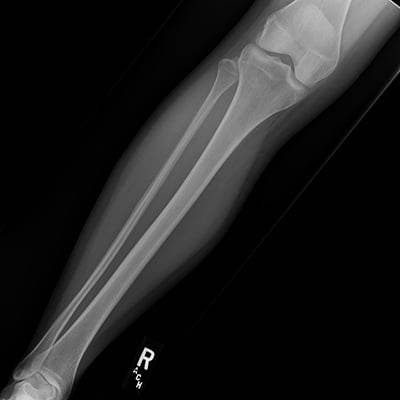

This module will help you achieve optimal images when performing tibia and fibula, knee, patella, and femur examinations. Patient preparation and positioning are discussed, as well as technical settings and patient instructions. Descriptions and images of the expected anatomical structures are included, as well as image evaluation criteria.